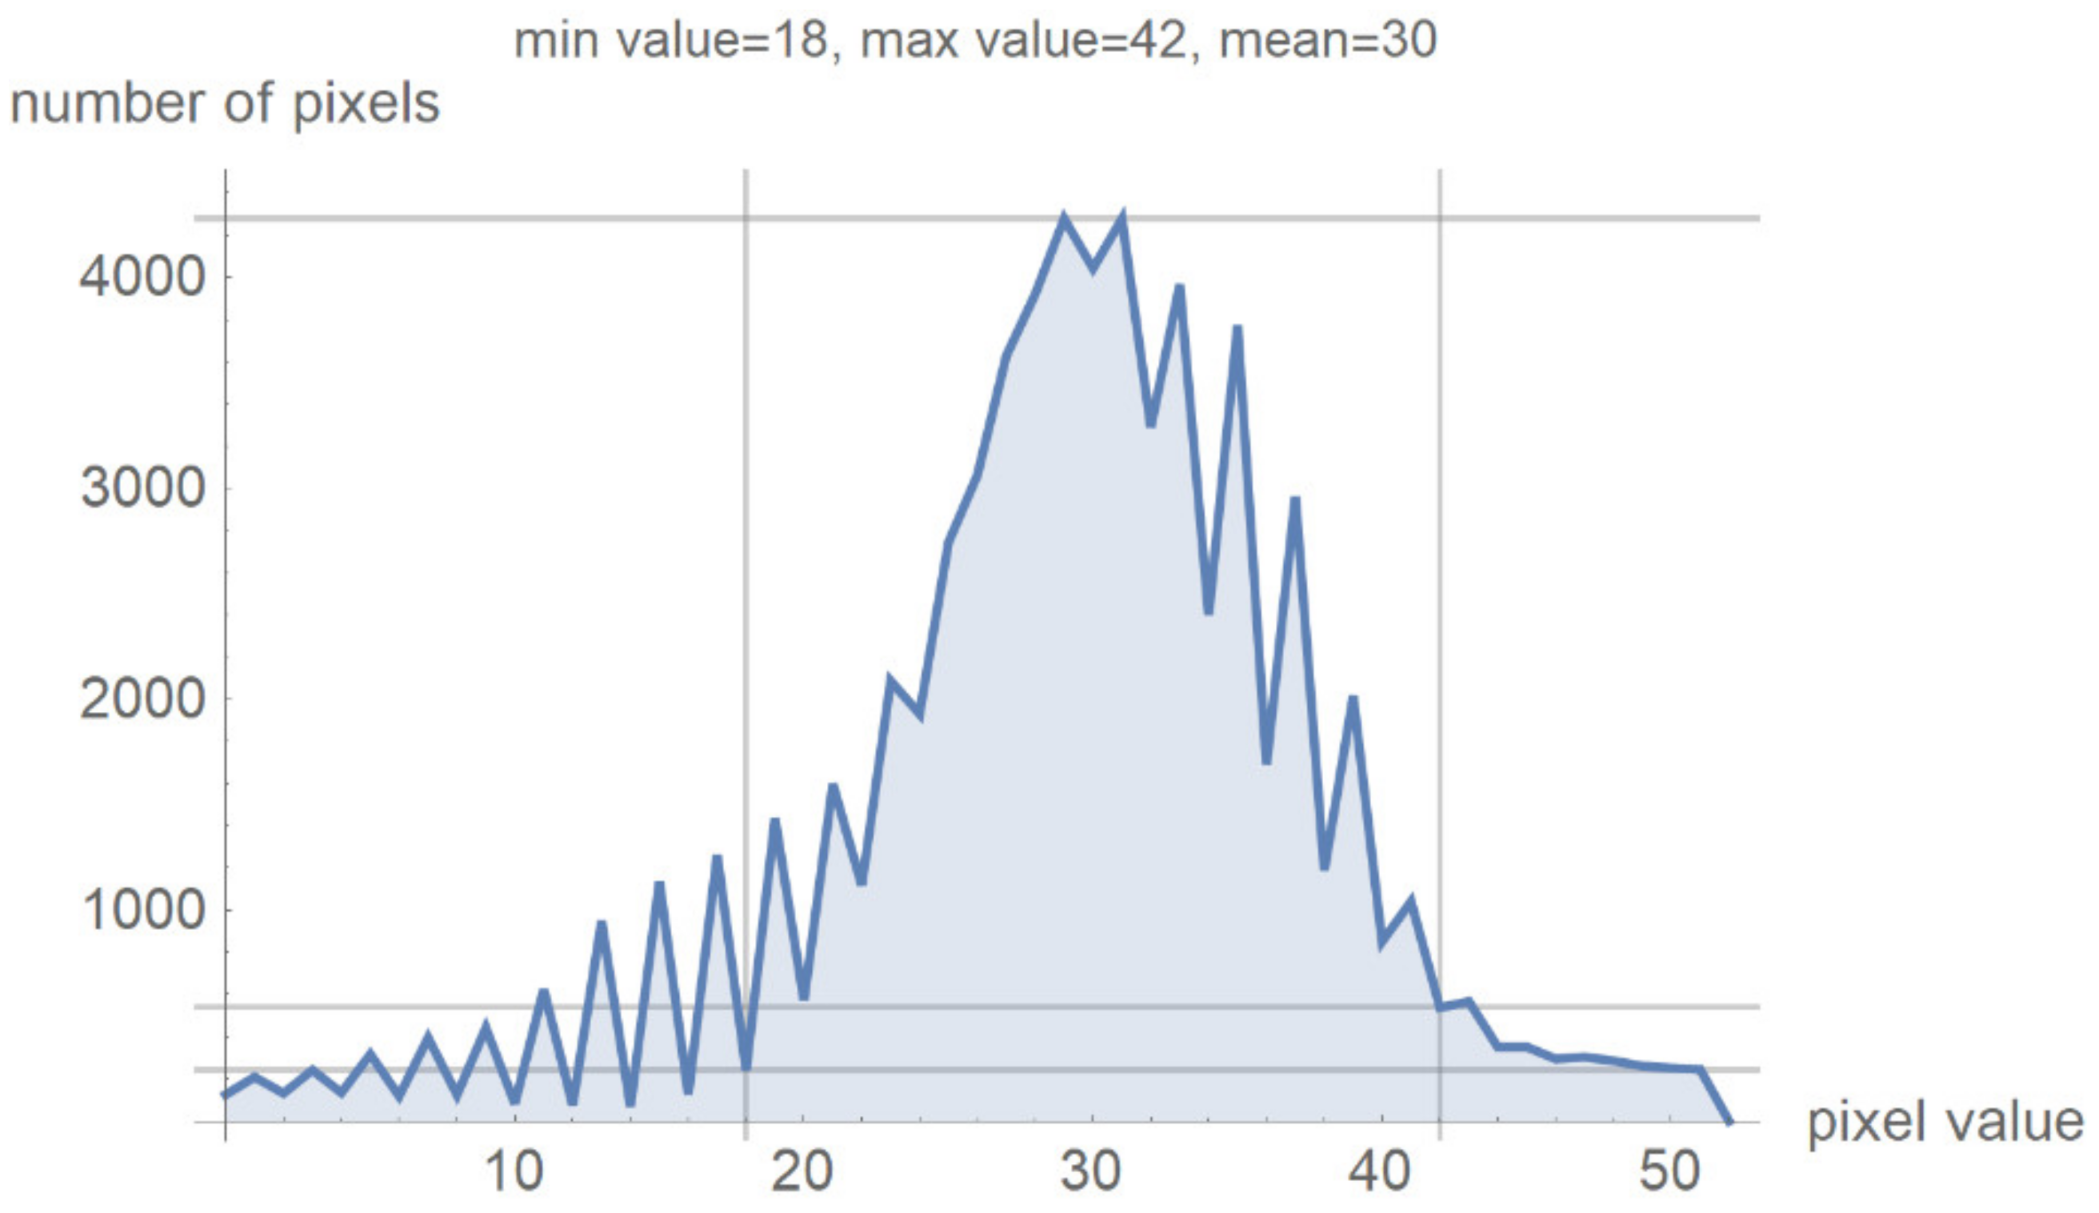

2.2. Smart Visualization Method (SVMI)

3.1. Technological Description